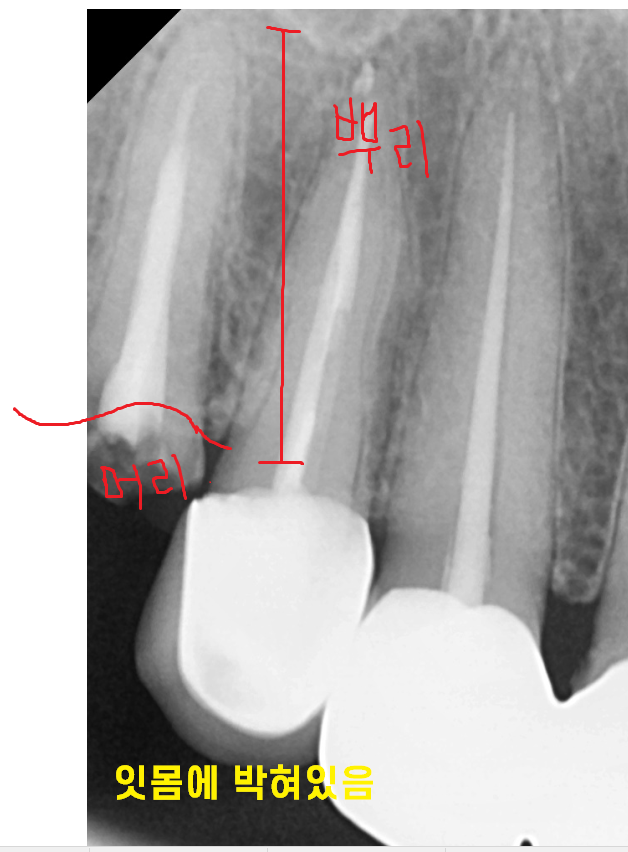

240313

머리 부분이 아주 조금만 남아있죠?

단단한 치아는 쉽게 부러지지 않는데요.

사람의 몸에서 제일 단단하거든요

(뼈보다 강합니다!!)

그런 치아가 보철과 함께 부러진거라면

이제 보내줘야합니다...

안타깝지만....